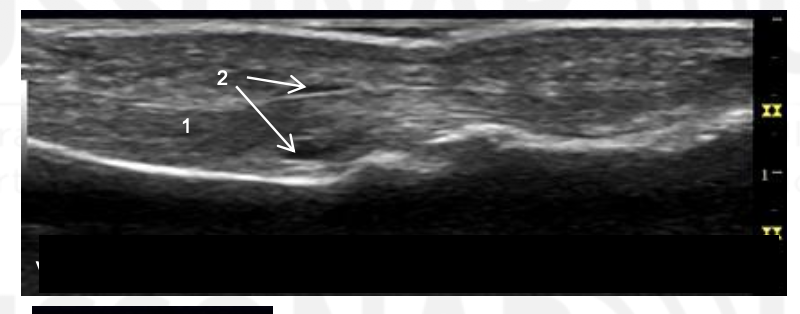

Name 1-4

Thickened A1 pulley

Tendon thickening compared to adjacent tendon. Also note tendon is thicker distal to A1 puley. On dynamic imaging, this impinged onto the A1 pulley.

MCP

Phalanx